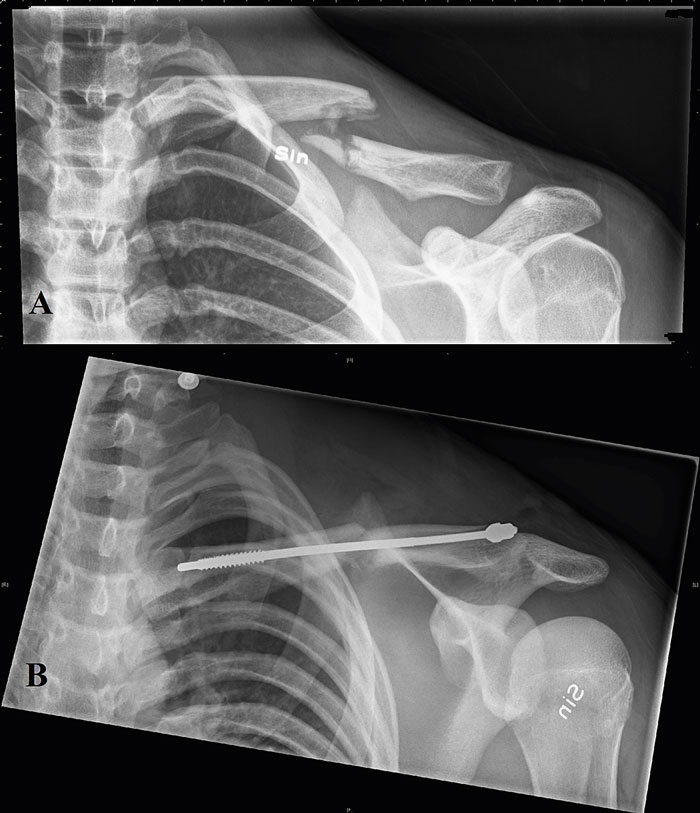

Anteroposterior projektion som visar fixation av en klavikelfraktur typ 2B2 (A) med en modern intramedullär kompressionspinne (B).